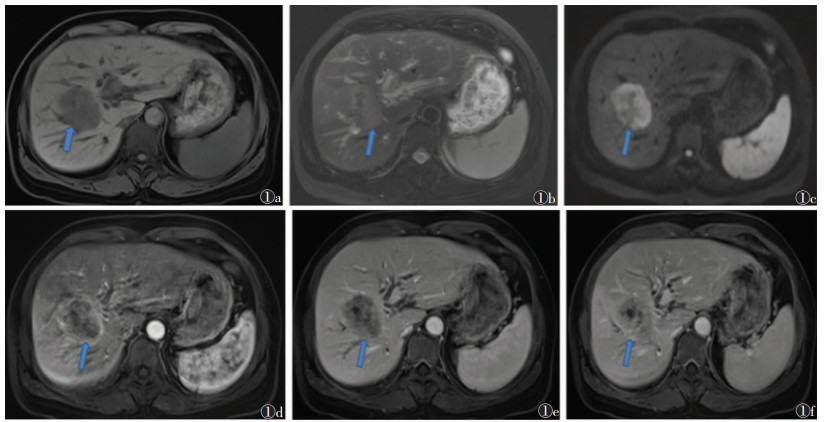

2 结果2组术前MRI表现见表 1,2组发病部位、强化模式、包膜、肝内胆管扩张、淋巴结转移方面比较,差异均有统计学意义(均P<0.05);2组肿瘤数量、最大径、信号特点、脉管瘤栓、肝内转移、肝硬化、门脉高压、腹水例数比较,差异均无统计学意义(均P > 0.05)。见图 1,2。

| 图 1 女,54岁,肝内胆管癌(ICC),AFP值为8.62 ng/mL 图1a 轴位T1WI示病灶位于肝右叶,呈类圆形,信号均匀,呈稍低信号 图1b 轴位T2WI脂肪抑制序列呈稍高信号,大小5.2cm×4.2cm,边缘模糊,形态欠规则 图1c DWI上病灶呈高信号 图1d 增强扫描动脉期病灶呈明显不均匀强化 图1e,1f 分别为门脉期、延迟期,病灶缓慢填充,表现为渐进性强化(箭头) |